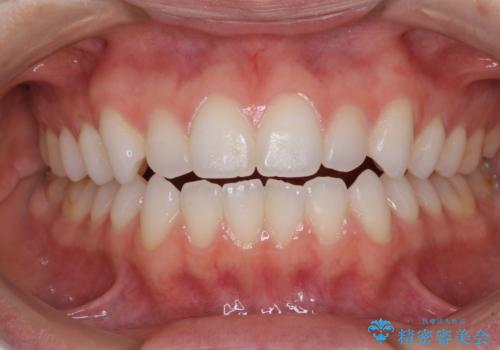

上下前歯が接触しない オープンバイトをインビザラインで改善

- 前歯の上下スペースによる食べにくさを気にして来院された患者様です。

インビザラインにより上下の前歯の隙間を閉じていくこととしました。

上下の奥歯を圧下させるようにすることで、前歯を接触させるように計画しました。